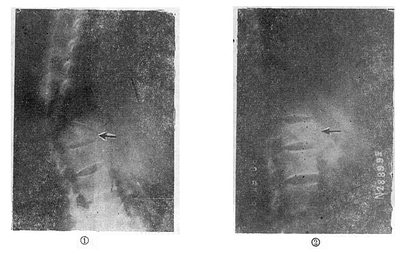

(五)切片状骨折的治疗 因为这种骨折伴有整个韧带的完全撕裂,且常合并截瘫,用Harrington撑开棍治疗后方间隙反而会明显增宽。应选用强度较好的Luque或Dick装置为好,不仅能获得满意的复位(图73-16①~③),而且固定牢固,术后即可随意翻动病人,术后1-2即可让病人起床坐轮椅活动,有利于截瘫病人的康复与护理。

切片骨折的治疗

图73-16 切片骨折的治疗